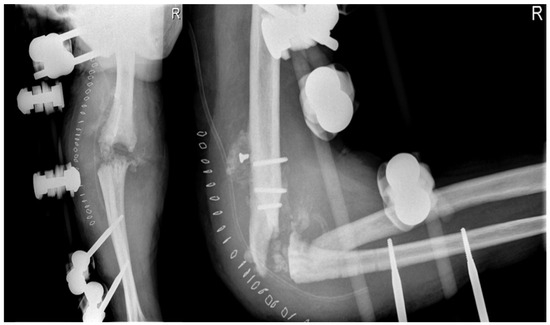

2.4.4. Arthrodesis

Arthrodesis and Complications